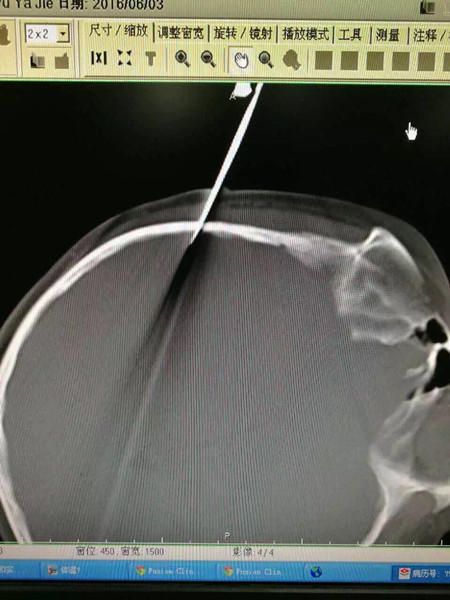

Хятадад нэгэн ууртай эцэг охиныхоо аминд хүрэх шахсан хэрэг гарчээ. 10 настай охин нь хичээлээ хийхийн оронд гадаа тоглож байжээ. Үүнд уурссан эцэг гарт барьсан зүйлээрээ охины толгойг цохьтол тэр нь хайч байж таарчээ. Харин хайч нь охины толгойн чамархай хэсэгт зоогджээ.

Энэ бүхний дараа охин ухаан алдан унаж юу болсныг санахгүй байжээ. Эмч нар түүнийг яаралтай мэс засалд оруулж хайчийг салган авсан байна.